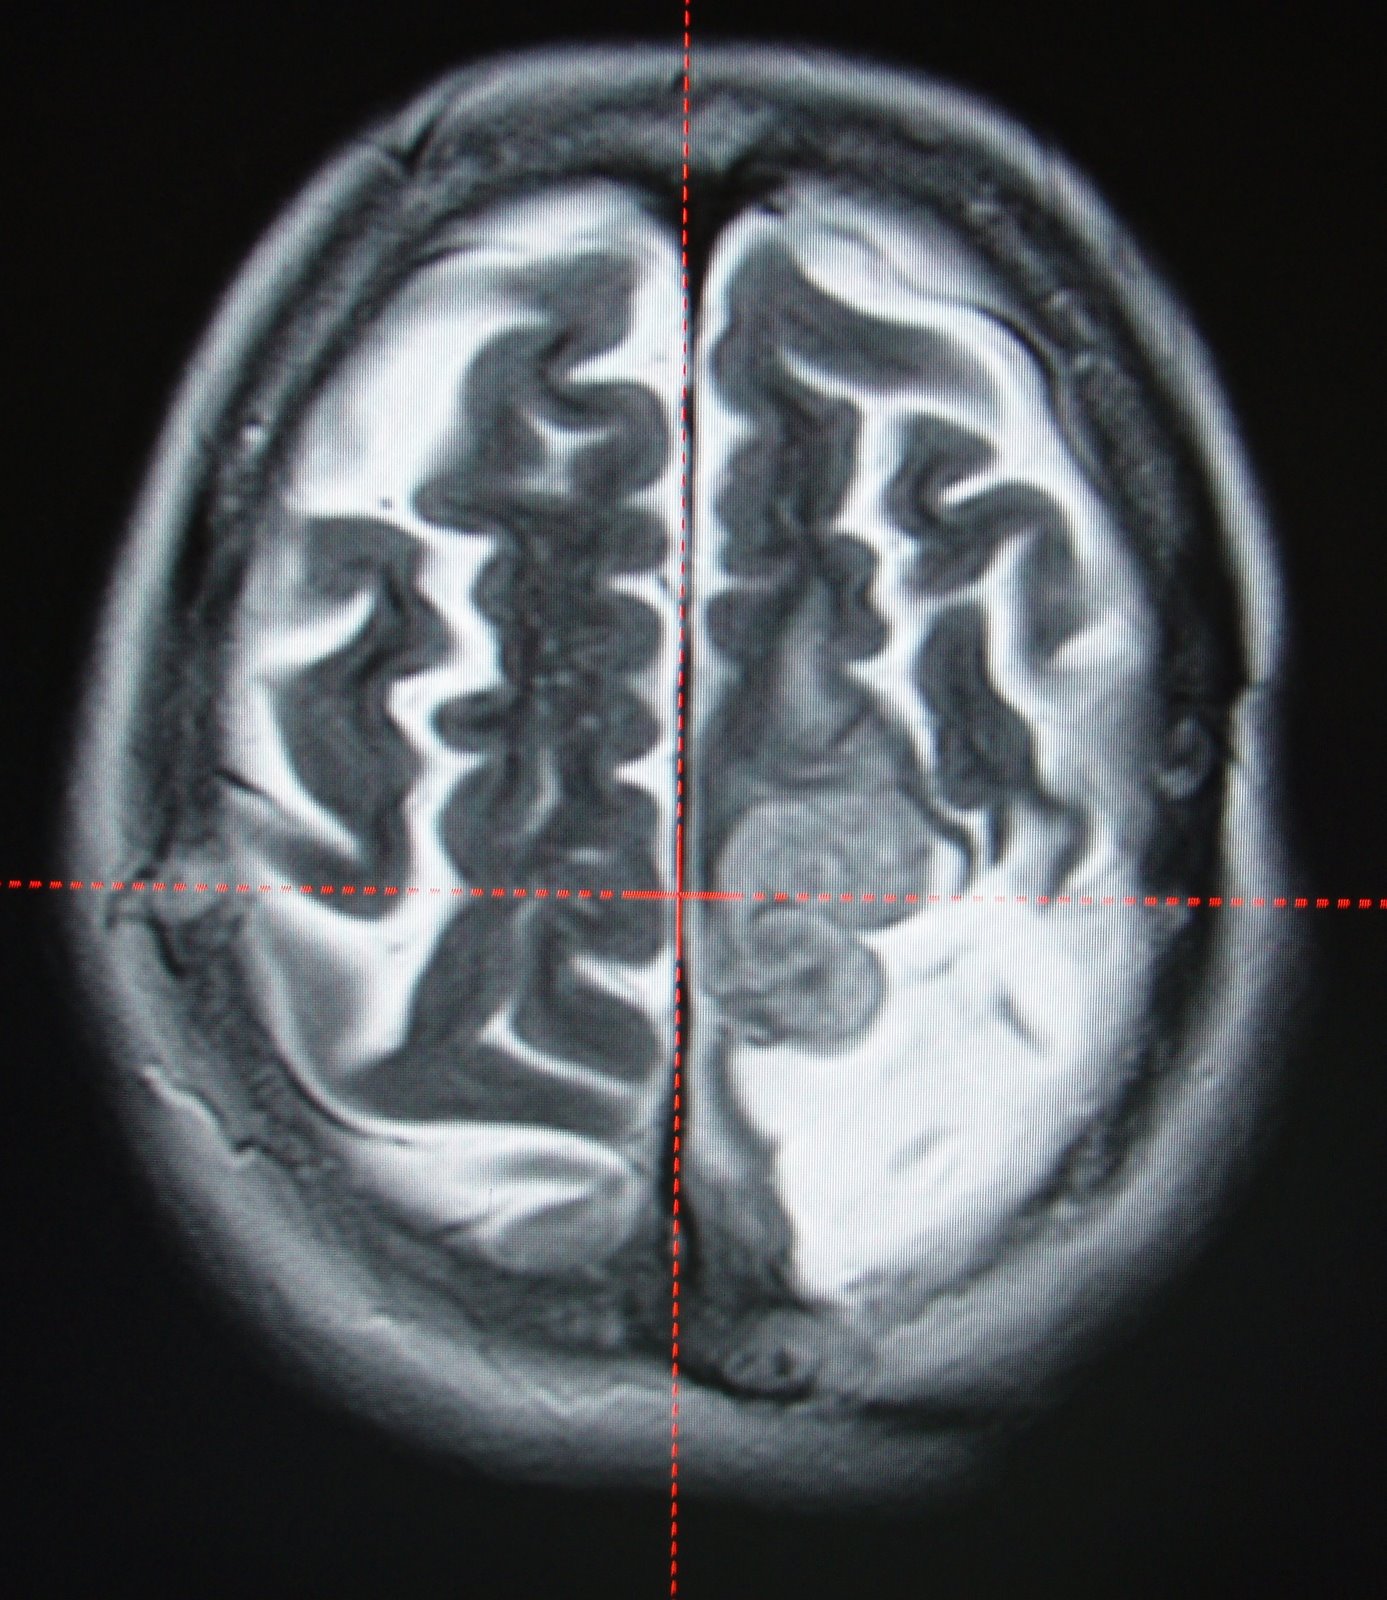

Meningioma (Lt.Parietal Recurrent).80% reduction in 2 yrs.

She is 54 yrs old Lady with recurrent left Parietal convexity Meningioma.She was treated with marginal dose of 12.0 Gy with 50% isodose line was prescribed for the target volume 29.2 cc.

Meningioma reduced to 7.1 cu. cm from 29.2 cu.cm

in two years time.